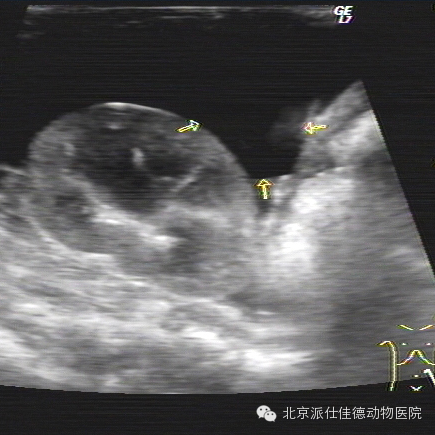

14.有些动物突然出现贫血,也没有发生外伤,腹围突然增大,经检查发现内脏大出血,最常见的是血管瘤破裂,如脾脏肿瘤破溃、肝脏肿瘤破溃、主动脉夹层瘤破裂等等。